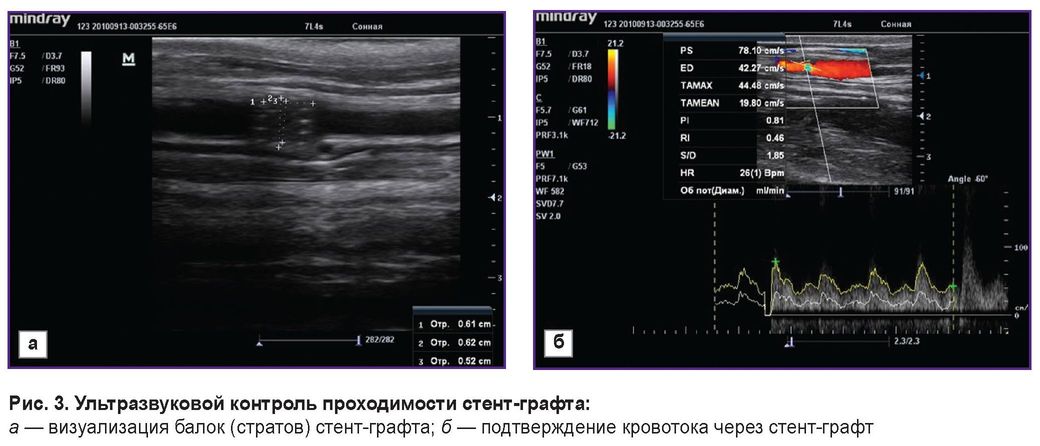

С целью оценки проходимости установленных стентов и стент-графтов на 3-и сутки, через 1 и 3 мес всем животным проводили УЗИ. Полученные результаты подтвердили проходимость всех имплантированных изделий: стенты и стент-графты визуализировались хорошо, отчетливо были видны балки (страты) (рис. 3, а). Кровоток через имплантированный стент-графт сохранен (рис. 3, б). Случаев тромбоза не зафиксировано.

Рис. 3. Ультразвуковой контроль проходимости стент-графта: а — визуализация балок (стратов) стент-графта; б — подтверждение кровотока через стент-графт |